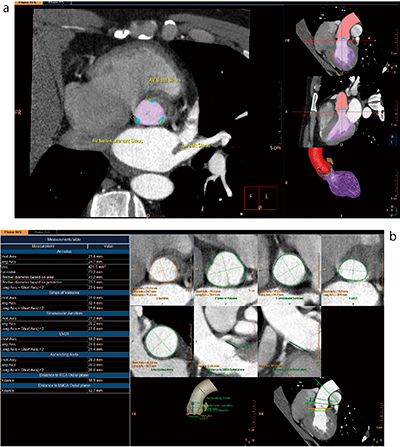

■TAVI-Planning

経カテーテル的大動脈弁植え込み術(transcatheter aortic valve implantation:TAVI)は,重症の未治療大動脈弁狭窄症に対する治療法としてヨーロッパで注目を集めた手技である。国内でも2013年10月に保険承認された治療法であり,TAVIを施行している医療機関が増えてきている。CTは三次元的な精度の高いデータの取得が容易なことから,SCCTのTAVI/TAVRガイドラインにもTAVI術前CTにおける画像計測の必要性が明記されている2),3)。

ISPには専用の解析アプリケーション“TAVI-Planning”(図3)を搭載することが可能である。TAVI術前情報として必須となる大動脈弁輪径,バルサルバ洞の計測,石灰化の有無・程度,デバイス選択のための大動脈弁輪の直径,弁先端部〜冠動脈起始部の距離の自動解析が可能である。これにより,解析者は装置が自動認識したランドマークを確認し確定するだけで,一連の解析に加え,Cアームのアングルシミュレーションも行うことが可能である。ISPでは,心室,心房,心筋など各部位を解剖学モデルを用いた自動セグメンテーションを行っているため,解析者の経験年数などに左右されることはなく,誰が行っても同じ解析結果になることをコンセプトとして設計されている。

図3 TAVI-Planning

a:セグメンテーションとランドマークの確認

b:測定結果。設定された面で設定されているすべての測定値を表示。